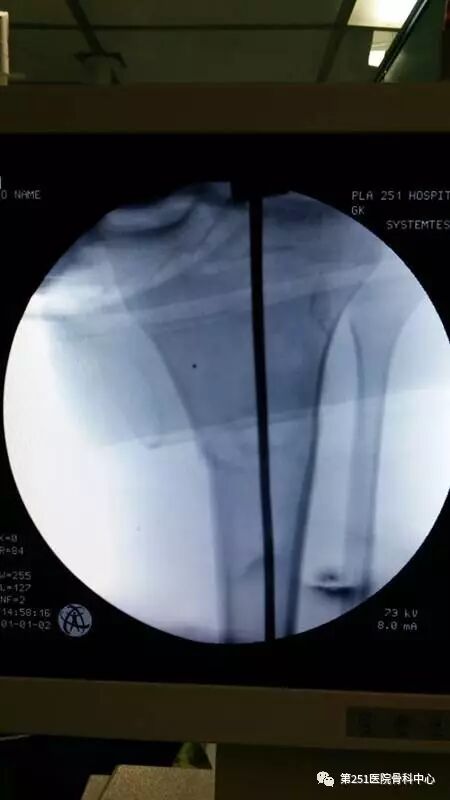

病例2:男性,44岁,车祸伤,双侧胫腓骨骨折(左侧)。